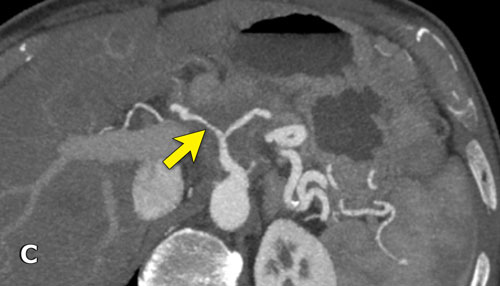

Hình tái tạo mặt phẳng đứng ngang (a) cho thấy một khối u nhỏ ở vùng bóng Vater (đầu mũi tên), gây tắc nghẽn cả ống mật chủ (CBD) và ống tụy (PD). Khi không có xâm lấn tại chỗ, tổn thương này được xem là có thể cắt bỏ được.

Tuy nhiên, hình CT axial (b) cho thấy phì đại của cung động mạch quanh tụy (các mũi tên), gợi ý mạnh hẹp đáng kể thân tạng.

Hẹp thân tạng được thể hiện trên hình MIP mặt phẳng đứng dọc (mũi tên trong c).

Dòng máu bàng hệ đến động mạch gan qua cung động mạch tụy-tá tràng (mũi tên nét đứt) được quan sát rõ trên hình MIP mặt phẳng đứng ngang (d).